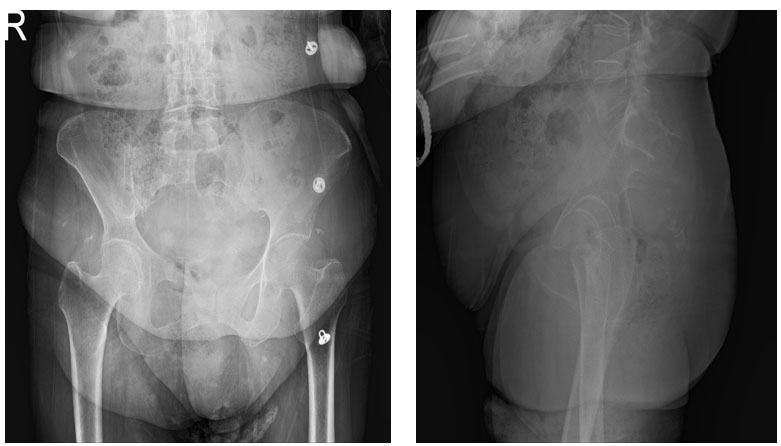

Ameliyat öncesi: Röntgende sakrumda ve koksiksde ciddi harabiyet görülmekte